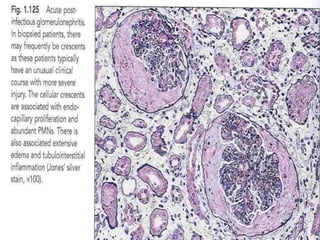

Light microscopy

 Light microscopy shows a diffuse proliferative

glomerulonephritis with prominent endocapillary

proliferation and numerous neutrophils.

 Trichrome stain may show small subepithelial hump-

shaped deposits.

 The severity of involvement varies and usually correlates

with the clinical findings.

 Crescent formation is uncommon and is associated with a

poor prognosis.

• Light microscopic findings

• Early stage → glomerular hypercellularity

• Later stage → Proliferation of intrinsic

endothelial & mesangial cells